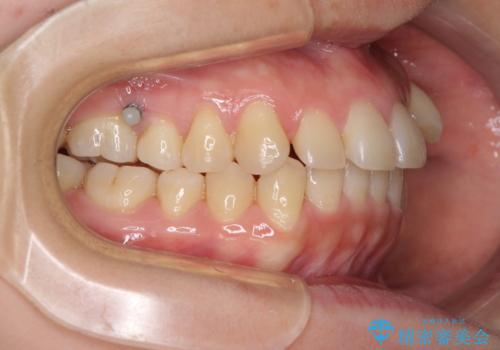

- 八重歯と前歯のデコボコを気にして来院された患者様です。

八重歯の他に、上顎歯列を狭窄しているという問題点がありました。

また、八重歯により上顎奥歯が前方に位置しており、咬み合わせの改善も必要な状況でした。

インビザラインによる矯正治療を希望されたため、上顎歯列の側方拡大奥歯の遠心移動のための補助装置を併用し、その後はインビザラインにて行うこととしました。